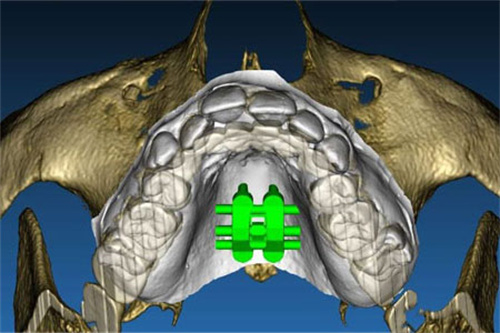

MSE扩弓器通过微种植钉辅助,实现了对上颌骨的快速扩展,为患者带来了显著的治疗结果。

MSE扩弓器能够显著扩大上颌基骨宽度,改善腭中缝的宽度,同时增加上颌牙弓宽度。研究表明,使用MSE扩弓器后,上颌基骨宽度、牙弓宽度及鼻腔容积等指标均有明显提升。

MSE扩弓不仅可以改善牙齿排列,还能对面部结构产生显著影响。它能够有效增加上颌软组织的形态,包括鼻部和颊部的宽度,从而改善面部的整体外观。

尽管MSE扩弓器对牙槽骨的影响较小,但仍可能引起一定的骨性副作用,如轻微的牙槽骨吸收和骨质密度不均等问题。这些副作用通常在治疗结束后会逐渐改善,但仍需患者注意。